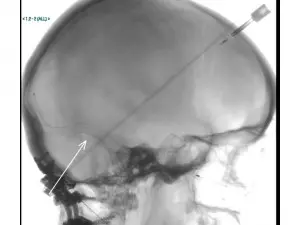

Fenner - Stent

Through two small needle pokes in the groin, Liu was able to successfully thread a stent into Fenner’s left transverse sinus, shown in the X-ray image at left. Once the normal flow of blood exiting the brain was restored, pressure within the skull dropped and Fenner experienced immediate relief. “The blurry vision was gone immediately, and I’ve been headache free since the procedure,” she says. “I’ve gotten my strength back, the whooshing in my ears is gone and my memory has improved. I’m cautiously optimistic.”